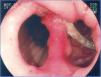

La incidencia de fístulas en la cirugía bariátrica varía con la técnica, con el número de pacientes y el período analizado y si se trata de series endoscópicas o quirúrgicas y estaba anteriormente estimada entre 0.4 hasta 26% de los casos21,49,81. Sin embargo, con la mejora de las cirugías hubo una disminuición significativa en esta tasa y se estima actualmente que las fístulas ocurran en 2.05 a 5.2% después de una derivación gástrica laparoscópica, en 1.68 a 2.60% después de una derivación abierta y en 0.6 a 7% después de una gastrectomía vertical82–85. Esta incidencia puede llegar hasta el 8% cuando la cirugía es realizada debido a una conversión de otra técnica59. Es una de las complicaciones más graves y es la segunda causa de muerte en la cirugía bariátrica, con una tasa de mortalidad de hasta 1.5%86,87. Las fístulas pueden ser gastrocutáneas, internas (gastrogástrica o gastroenteral) o pueden ser consideradas complejas, afectando la bolsa gástrica y algun órgano adyacente o distante87. La fístula gastrocutánea ocurre después de un cuadro precoz de sepsis abdominal, debido a peritonitis o absceso localizado, tratado con intervención quirúrgica y/o drenaje87. En la fístula gastrogástrica o gastrointestinal la manifestación clínica es tardía, con pérdida de peso inadecuada o con readquisición de peso, dolor epigástrico (debido a una úlcera marginal) y reflujo, pero puede ser subclínica, asintomática y con pérdida de peso satisfactoria13. La endoscopia define la presencia del orificio fistuloso y lo caracteriza en relación a su localización, tamaño del orifício interno y la presencia de cuerpo extraño (hilo de sutura) en la mucosa adyacente. La fístula gastrocutánea ocurre más comúnmente en la anastomosis gastroyeyunal y en la porción alta de la línea de sutura de la bolsa gástrica (derivación) o del muñon gástrico (gastrectomía), adyacente a la transición esofagogástrica (fig. 9), ciertamente por una deficiencia en la vascularización en este punto14,87. En la fístula interna observamos una amplia comunicación con el asa intestinal o con el estómago excluido (fig. 10). En las dos situaciones se puede diagnósticar una estenosis distal, relacionada con el anillo y a la anastomosis en la derivación gástrica o una angulación excesiva en la porción final de la zona tunelizada de la gastrectomía vertical. Estos factores son considerados predisponentes y mantenedores de las fístulas86. La endoscopia puede identificar otras alteraciones como la migración interna del anillo en la derivación, tortuosidad y dilatación de la porción tubular en la gastrectomía vertical y la presencia de septos de mucosa adyacentes al orificio fistuloso. El estudio contrastado de la fístula puede ser realizado para la demostración y delimitación del trayecto fistuloso, diagnóstico de comunicaciones con otros órganos, diagnóstico de fístulas complejas y, especialmente, para la evaluación de la dificultad del vaciamiento relacionada con estenosis distales a la fístula13,19. Las fístulas, después de las cirugías bariátricas, son tratadas con soporte nutricional, supresión de las secreciones gastrointestinales, tratamiento de la infección y excisión quirúrgica del orificio fistuloso14. La endoscopia puede ayudar en estas medidas generales con procedimientos como el pasaje de una sonda nasoentérica que permite la nutrición, excluyendo así el tránsito en la región de la fístula, remoción de cuerpos extraños en la región del orificio, colocación, tracción y reposicionamiento de los drenajes o sondas en las cavidades y colecciones y, sobre todo, tratando eventuales estenosis distales a la fístula84. Este tipo de tratamiento es de considerable valor y permite conllevar al cierre de hasta el 85% de las fístulas88. Sin embargo, algunas veces este abordaje puede ser demorado, de alto costo y no lograr el éxito esperado. En estos casos se sugiere el tratamiento endoscópico específico dirigido a la fístula gastrocutánea que puede llevar al cierre o contribuir para una resolución más rápida, disminuyendo el tiempo de internación y la morbilidad86. El cierre de la fístula puede requerir la oclusión no solo del orificio fistuloso, sino de todo su trayecto. Esto ha sido intentado con la inyección endoscópica de sustancias como pegamentos biológicos o sintéticos, colocación de matriz acelular en forma de tiras o conos en el trayecto o en el orificio fistuloso, aplicación de endoclips y en casos especiales con la colocación de prótesis autoexpandibles13,14,86. Más comúnmente, se utiliza una combinación de técnicas. Para indicar una técnica endoscópica de tratamiento de fístulas es necesario cerciorarse que el factor de mantenimiento de la misma haya sido resuelto, como infección, cuerpo extraño y obstrucción distal. Una de las opciones de tratamiento endoscópico de las fístulas poscirugía bariátrica es la colocación de prótesis autoexpanbibles, parcial o totalmente recubiertas86,89. En el caso de las fístulas poscirugía bariátrica es necesario utilizar prótesis especiales que pueden ser removidas90. Inicialmente fueron usadas las prótesis plásticas y después las metálicas89,90. La prótesis autoexpandible recubierta forma una barrera física entre la fístula y el contenido endoluminal, favoreciendo la cicatrización mientras permite la nutrición enteral91. Poli et al.92 revisaron 67 casos de fístulas después de derivaciones gástricas en Y de Roux, de gastrectomías verticales, de switch duodenal y de gastroplastias verticales con bandas tratados con la colocación de prótesis. Los resultados mostraron cierre de las fístulas en el 87.7% de los casos, con un rango entre 79 a 94% (intervalo de confianza de 95%). El intervalo de tiempo entre la colocación y la retirada de las prótesis, varió en la mayoría de los estudios entre uno y 2 meses. Seis de los 67 pacientes (9%) fueron sometidos a tratamiento quirúrgico tras el fracaso del cierre con la colocación de hasta dos prótesis. Hubo migración del stent en 16.9% de los casos, relacionada al diseño de las prótesis o tipo de cirugía, y no con la técnica endoscópica de la colocación. La remoción endoscópica de las prótesis fue posible en casi 92% de los casos, las causas de falla fueron hiperplasia del tejido y migración. Hay relatos de dificultad en la retirada de las prótesis, con complicaciones graves como hemorragia, remoción en pedazos e incluso mucosectomía. Existen casos de colocación de prótesis plástica dentro de la prótesis metálica para facilitar su remoción93. Considerando las dificultades y complicaciones de la retirada, de la tasa de migración y de los distintos detalles anatómicos de las técnicas quirúrgicas, será necesario el desarrollo de prótesis específicas para que sean utilizadas en las fístulas poscirugía bariátrica86,91. Aunque el tratamiento de las fístulas con prótesis parece promisor, todavía faltan datos controlados para recomendar su uso rutinário14,90. Estos accesorios deben tener tamaño y calibre diferenciados (adaptados a la anatomía quirúrgica), sistema antimigración y mecanismo de remoción seguro o que sean biodegradables13,86,90. Por fin, nos parece que la tendencia para el papel de la endoscopia en las fístulas será en dos situaciones: primero en la colocación de prótesis en los casos precoces93, segundo en la dilatación vigorosa de eventuales estenosis distales en los casos crónicos19. En los casos de fístulas gastrogástricas y gastrointestinales el tratamiento clásico es quirúrgico, que puede cursar con una morbimortalidad dos veces superior a la primera cirugía. Considerando los problemas de las reintervenciones quirúrgicas, inclusive el fracaso en el cierre de las fístulas, se sugiere el tratamiento endoscópico. En los últimos años, publicaciones con pequeñas series o relatos de casos muestran la posibilidad de la sutura endoscópica de estos defectos, utilizando accesorios como el Endo-Cinch94, clips especiales (Ovesco)95, StomaphyX96 y Apollo OverStitch97 o el intento de cierre del orificio utilizando prótesis, pegamento biológico y debridamiento por coagulación con argón plasma y algunas veces utlizando una combinación de dos o más métodos90. Todas las técnicas se muestran factibles, aunque la durabilidad de estas suturas endoscópicas todavía carece de evaluación y de seguimiento a largo plazo, especialmente en las grandes comunicaciones de la bolsa con el estómago y/o el intestino86,90.